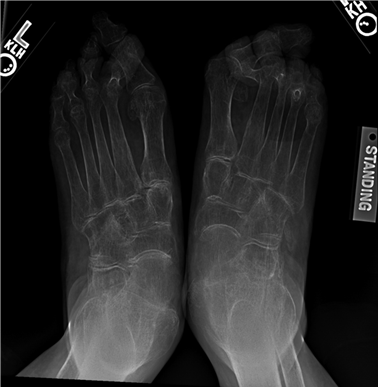

Epidemiologically, hallux valgus alone affects nearly 23% of adults aged 18 to 65 years and over 35% of individuals older than 65 years, with a pronounced predilection for the female demographic. This gender disparity is classically attributed to a combination of intrinsic ligamentous laxity, hormonal influences, and extrinsic factors such as constrictive, narrow-toebox footwear with elevated heels. However, modern orthopedic consensus increasingly acknowledges the polygenic, hereditary nature of first ray deformities. Patients frequently exhibit a positive family history, suggesting an underlying genetic predisposition to metatarsus primus varus, hypermobility of the first tarsometatarsal (TMT) joint, or anomalous articular morphology.

Weight-bearing anteroposterior (AP), lateral, and sesamoid axial radiographs are mandatory. On the AP view, the surgeon measures the Hallux Valgus Angle (HVA, normal < 15°), the Intermetatarsal Angle (IMA, normal < 9°), and the Distal Metatarsal Articular Angle (DMAA). The lateral view is scrutinized for Meary's angle (talo-first metatarsal angle) to identify midfoot collapse, as well as the presence of dorsal osteophytes indicative of hallux rigidus. The sesamoid axial view is critical for assessing the degree of sesamoid subluxation and the integrity of the crista.

Image